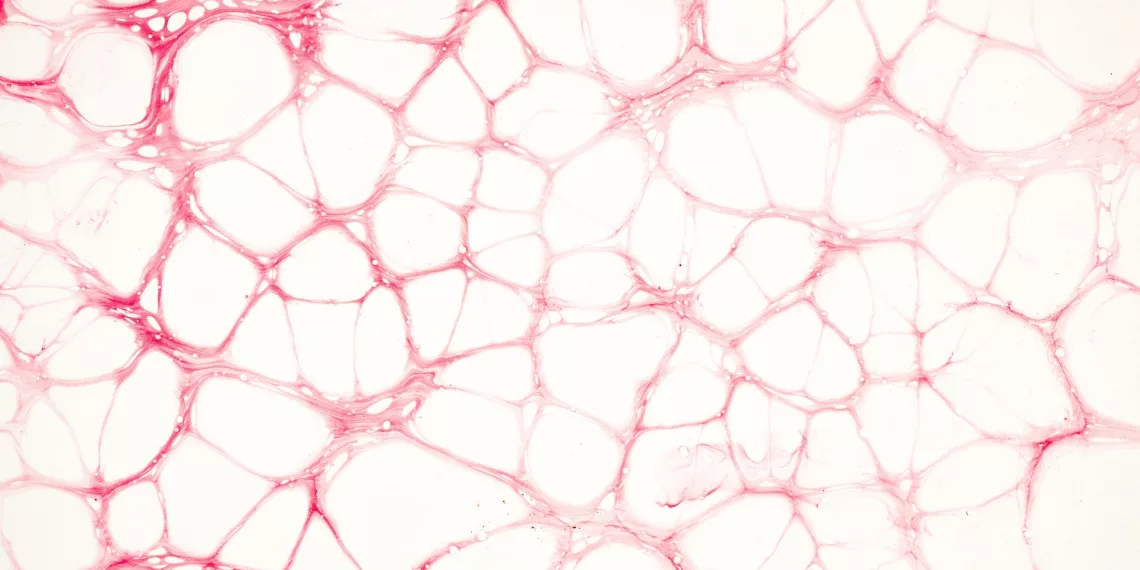

Напомним, что разработанный полимер позволит заполнить патологические сосудистые сплетения, чтобы исключить вероятность их разрыва.